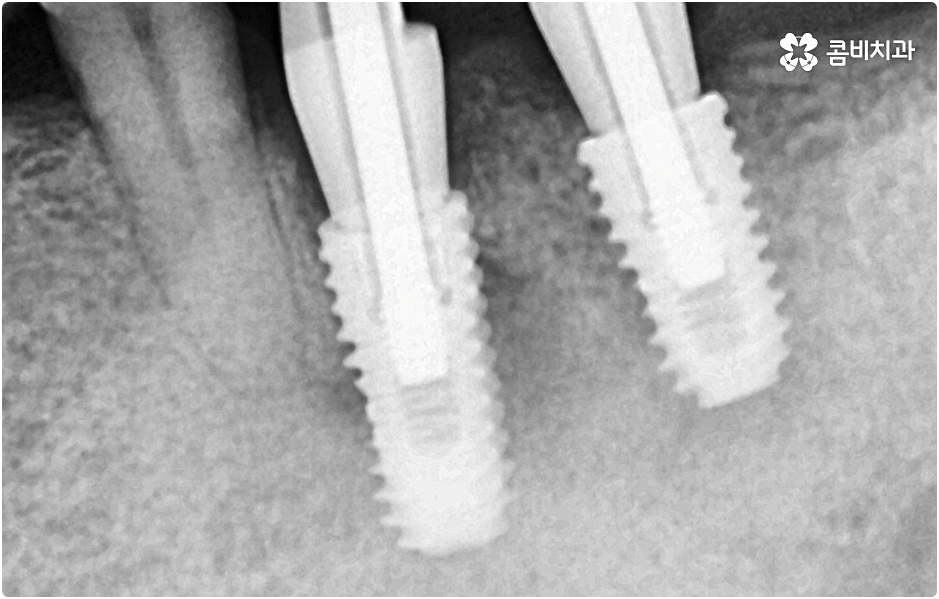

임플란트 시술을 받을 때 치아를 상실한 원인이 무엇인지, 상실하고 나서 그대로 둔 시간이 얼마나 되는지, 현재 치아나 잇몸 등 구강 내부 상황이 어떤지 등등을 먼저 꼼꼼하게 파악할 필요가 있는데요. 예를 들어 20대임플란트 를 받게 된 원인이 사고와 같은 외부 충격으로 인한 것이고 시간이 많이 흐르지 않은데다 다른 구강 질환 (충치나 치주 질환) 이 크게 문제가 되지 않는 상황이라면 젊은 나이이기 때문에 바탕이 되는 잇몸뼈 건강이 비교적 양호할 것이라고 예상할 수 있으며 이런 경우 즉시 임플란트 방식을 검토해 볼 수 있어요. 면밀한 정밀 검사 후 가능하다는 의료진의 진단이 내려진다면 당일에 인공 치근을 심고 임시 크라운까지 올려 바로 사용할 수 있는 즉시 임플란트 방식을 통해 보다 빠르고 간편하게 수복을 할 수 있습니다.

그러나 나이가 젊다고 해도 만약 치아를 상실한 원인이 심각한 구강 질환으로 인한 것이거나 치아를 잃고 나서 오랜 시간 방치를 하였거나 평상시에 당뇨 또는 고혈압 등을 앓고 있었다면 환자분의 잇몸뼈 건강이 양호하지 않을 수 있으며 그런 경우에는 즉시 임플란트 시술을 받을 수 없고 먼저 뼈이식 과정을 통해서 잇몸뼈를 보충해 준 다음 20대임플란트 식립을 진행하는 것이 정확도와 지속성을 높여주는 방법이라고 할 수 있어요.

그러나 언급했던 것처럼 잇몸뼈 상태에 대해서 먼저 체크해 봐야 하기 때문에 누구나 받을 수 있는 치료 과정은 아니라는 점을 분명히 알아두실 필요가 있습니다. 이렇게 잇몸뼈를 보충해야 하는 상황 뿐 아니라 충치 또는 치주 질환을 먼저 깨끗하게 치료해야 하는 상황, 상악동까지의 거리가 너무 짧아서 거상술을 통해 혹시 모를 천공과 염증을 방지해야 하는 상황 등 여러 가지 선치료가 필요한 케이스들이 있을 수 있기 때문에 먼저 환자분들의 상황을 자세하게 파악하기 위해서 꼼꼼한 검진을 해 볼 필요가 있으므로 3D CT 등 정밀 검진 장비 보유 여부가 필수적이라고 말씀드린 거예요.